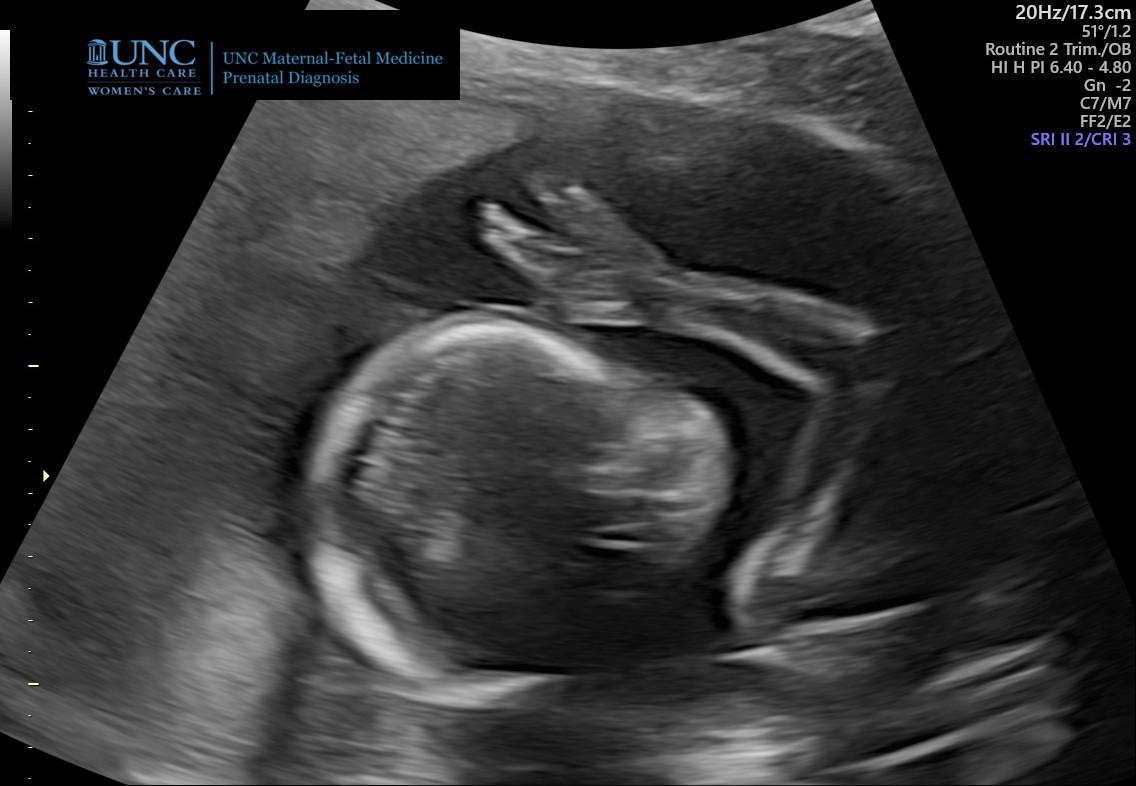

Related: Culture Forums, Support ForumsOH MY ... my soon to be new grandson is a Trekkie

Hell be a Virgo, not a Vulcan 🖖

but wait Aug 23 is the festival of Vulcanalia and the beginning of the time of those born under the sign of Virgo 🤔

OH MY